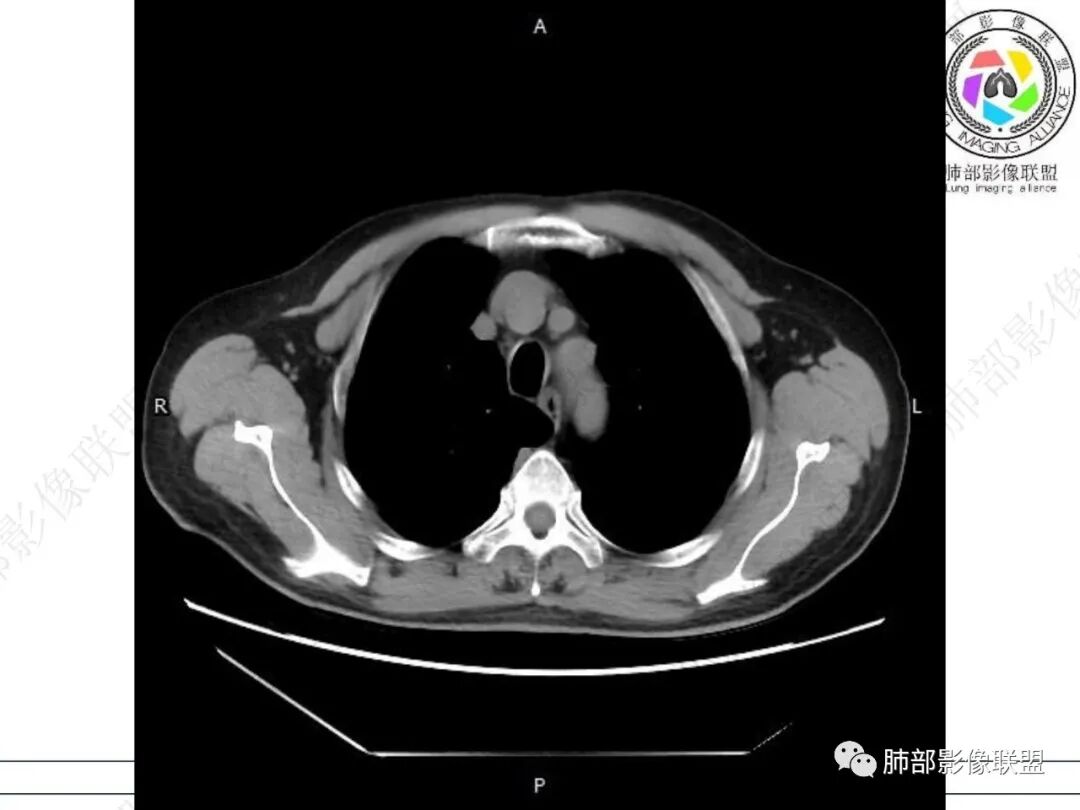

右肺下叶背段可见斑片状、条片状高密度影,支气管扩张,周围伴有磨玻璃影,边界欠清,纵隔窗:可见脊柱偏右侧可见斑片状影,与食管交界面欠清,食管形态不规则,考虑食管支气管瘘?食管异物穿孔?支气管异物?建议食管镜及支气管镜检查。

气管隆突下团片影,其内积气,与食道分界不清,食道壁增厚,管腔狭窄,右下肺实变影,支气管壁增厚,考虑食管支气管瘘并右下肺感染,食道肿瘤病变不除外

右肺下叶背段条片状实变影,内可见支气管走行,支气管有狭窄有扩张,周围可见磨玻璃影,隆突下团片影,内密度不均可见气体影,与周围结构界限不清。食管下段壁增厚,管腔狭窄,右肺下叶慢性炎、肺不张,考虑食道肿瘤所致气管食管瘘。

老年男性,慢性病程,右肺下叶斑片影、斑点影、实变影,支气管轻度扩张,病灶整体稍收缩;食道壁增厚、肿胀、模糊,气管隆突及右后纵隔旁见软组织块影,其内见气泡影,均匀强化,符合食道支气管瘘伴周围炎症,右下肺炎症

右肺下叶沿肺叶肺段分布斑片、条片状影,以下叶背段为显,边缘模糊,内可见支气管走行,局部支气管管壁增厚,右侧胸腔少量积液。纵隔隆突下可见不均匀软组织密度影,与周围结构分界不清,内见气体密度影,与食管及相邻右肺支气管之间未显示通道。邻近食管下段壁明显不规则增厚,增强后食管管壁明显不均匀强化,可见线样强化的连续完整粘膜影。